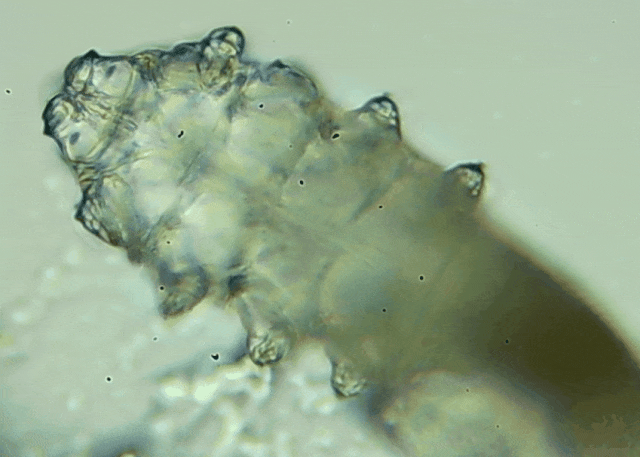

蠕形螨是一類肉眼看不見的寄生螨,常見的有毛囊蠕形螨和皮脂蠕形螨,常駐在人類的毛囊和皮脂腺里,尤其是眼睛的瞼板腺和睫毛根部。數(shù)量少時(shí),蠕形螨能與人體“和平共處”,但一旦你免疫力下降、油脂分泌旺盛或清潔不到位,他們就會(huì)以你難以想象的速度瘋狂繁殖。

廈門眼科中心羅順榮【文章導(dǎo)讀】我只是眼睛癢,結(jié)果醫(yī)生說我睫毛里有80只蟲?這不是恐怖片,而是真實(shí)的病例:武漢一13歲男孩,右眼9根睫毛里檢出39只螨蟲,左眼9根里檢出47只。 而且這不是極端個(gè)案,廈門眼科中

而且這不是極端個(gè)案,廈門眼科中心干眼門診的臨床數(shù)據(jù)統(tǒng)計(jì),眼睛經(jīng)常紅癢發(fā)炎的人群,多數(shù)都有螨蟲,約80%以上的瞼緣炎患者螨蟲超標(biāo),一根睫毛最多能有幾十只。